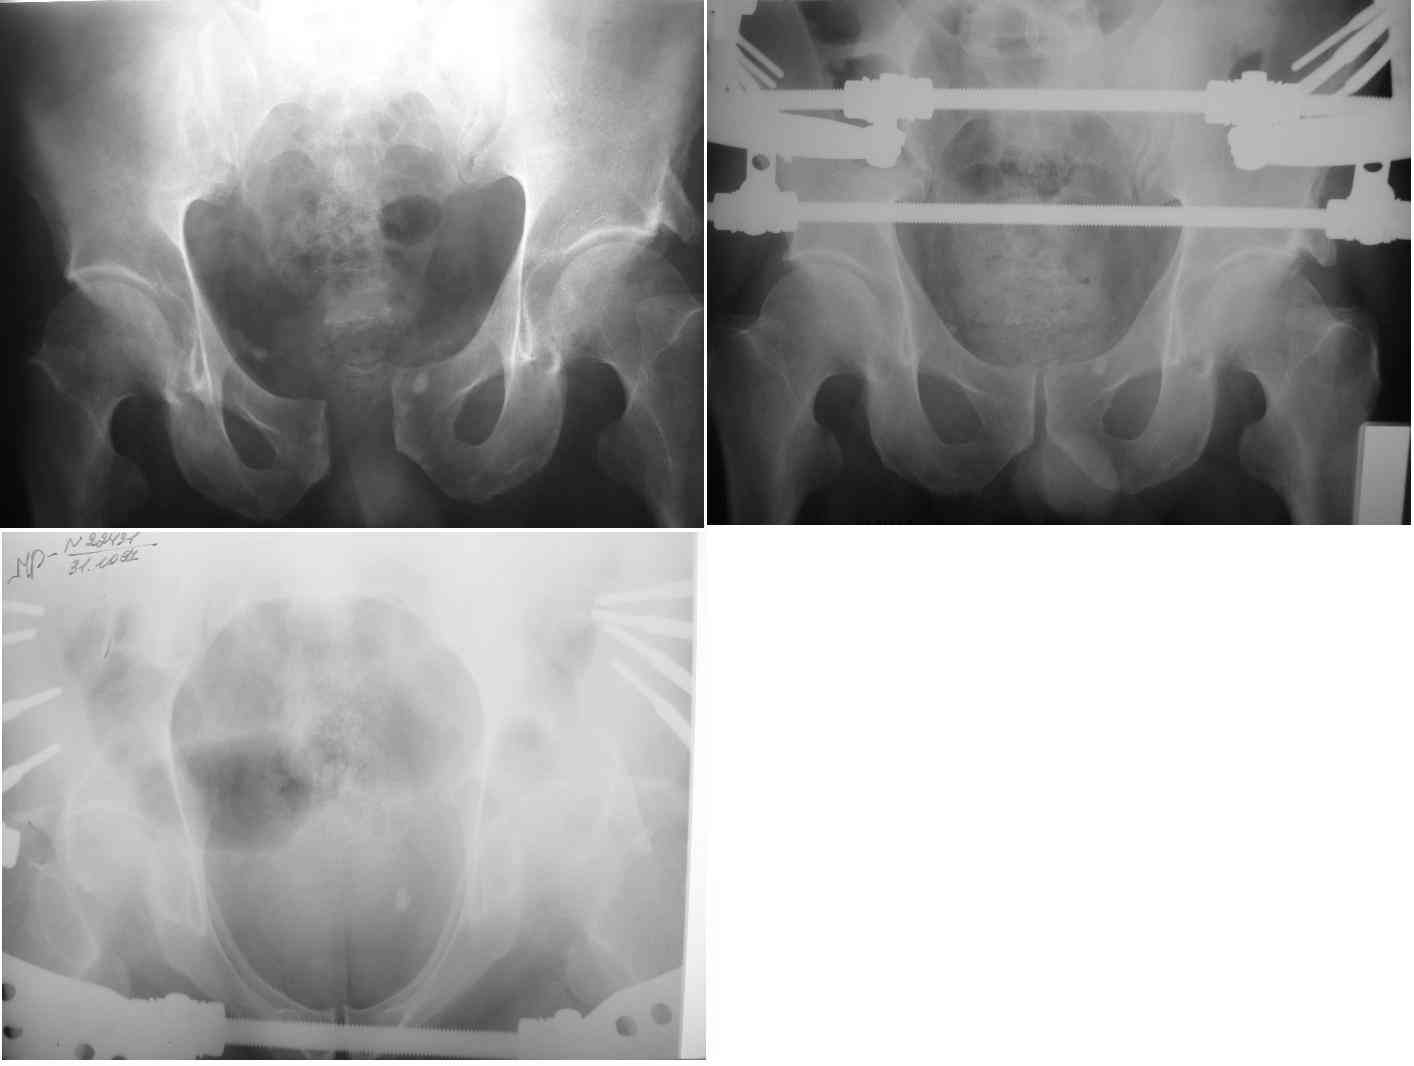

Re: разрыв лонного сочленения

извините за опоздание , вот фотографии

Репозиция действительно очень неплохая, но чтобы уменьшить риск развития поздней нестабильности, в такой ситуации лучше выполнить синтез лонного сочленения пластиной и оставить аппарат месяца на 2.

Уважаемый Максим, извините незнаю вашего отчества, я согласен с тем что дополнительно нужно установить пластину. Мне необходимо научное (литературное) обоснование следующего этапа (остеосинтеза пластиной лонного сочленения), т.к. стаж у меня всего 3 года а начмеда убедить моих доводов, и то что в интернете выкопал (как говорит начмед) маловато.